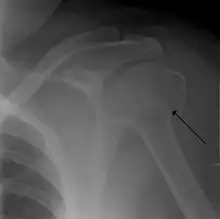

Fracture dislocation of the right shoulder

Proximal humerus fracture